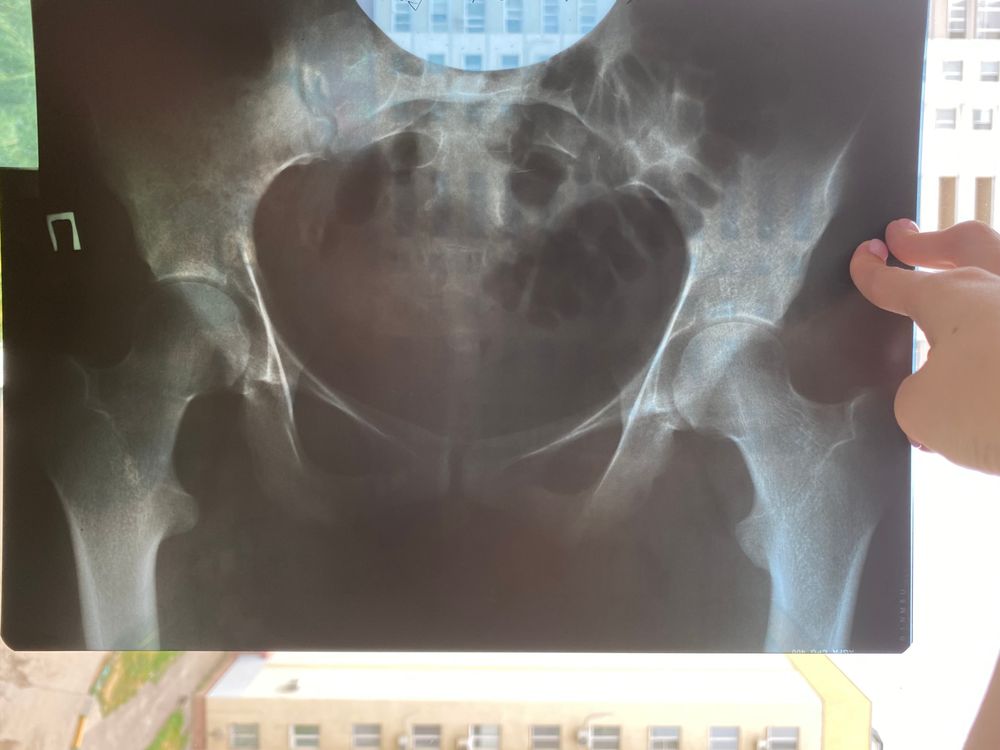

Снимок тазовых костей от 11 января 2019 года прикрепила

Привет! Сегодня ездили подписывать обменную карту в 4 роддом на одесской 46а. Мой ортопед, который лечил сколиоз (с 12 по 16год) сразу сказал, что всвязи с перекосом таза естественные роды запрещены. Затем мы ходили к ортопеду в поликлинику на Лисина и он так же посмотрев снимок выписал справку о том, что родоразрешение естественным путем не рекомендовано.